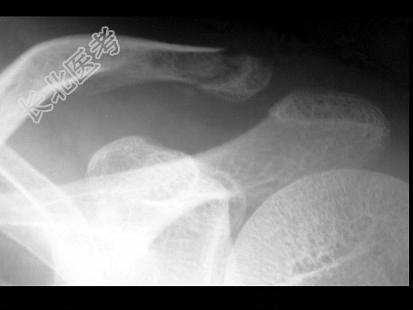

- 单项选择题男,25岁, 外伤后摄片,请结合影像图像选择最可能的诊断 ( )

A、肋骨骨折

B、锁骨骨折

C、原发性气胸

D、肋骨骨折伴气胸

E、锁骨骨折伴气胸